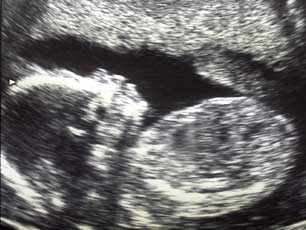

The abortion debate asks whether it can be morally right to terminate a pregnancy before normal childbirth.

Some people think that abortion is always wrong. Some think that abortion is right when the mother's life is at risk. Others think that there is a range of circumstances in which abortion is morally acceptable.